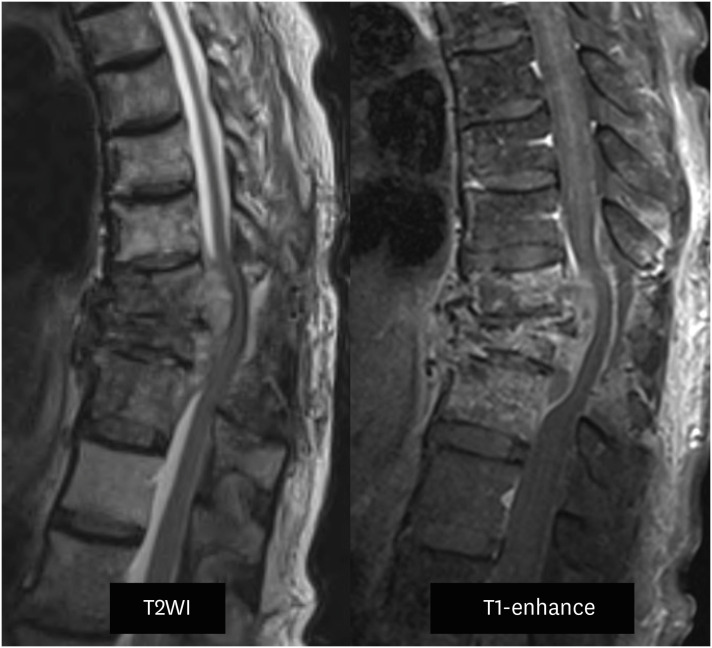

结核性脊柱炎,又称波特病,于1779年由珀西瓦尔·波特首次描述。由于感染的非特异性,结核性脊柱炎的诊断常常被推迟,这可能导致严重的后果。鉴别诊断对化疗后出现淋巴结或骨转移的癌症患者尤为重要。我们提出的情况下,76岁的女性胃癌晚期,谁最初怀疑有转移性脊柱肿瘤和细菌性脊柱炎。患者表现为下肢瘫痪,并被诊断为转移性癌症,导致失去康复的希望。然而,在随后的结核性脊柱炎诊断和多次手术干预后,患者完全缓解并显著改善,最终恢复了独立行走的能力。这个病例强调了准确诊断和及时干预的重要性,在病例的最初表现可能模仿转移性疾病。

Tuberculous (TB) spondylitis, also known as Pott's disease, was first described by Percivall Pott in 1779. The diagnosis of TB spondylitis is often delayed because of the non-specific nature of the infection, which can lead to severe consequences. Differential diagnosis is especially critical in cancer patients undergoing chemotherapy who present with lymph node or bone metastasis. We present the case of a 76-year-old female with advanced gastric cancer, who was initially suspected of having a metastatic spinal tumor and bacterial spondylitis. The patient presented with lower limb paralysis and was diagnosed with metastatic cancer, resulting in a loss of hope for recovery. However, following the subsequent diagnosis of TB spondylitis and multiple surgical interventions, the patient achieved complete remission and significant improvement, ultimately regaining the ability to walk independently. This case highlights the importance of accurate diagnosis and timely intervention in cases where the initial presentations may mimic metastatic disease.